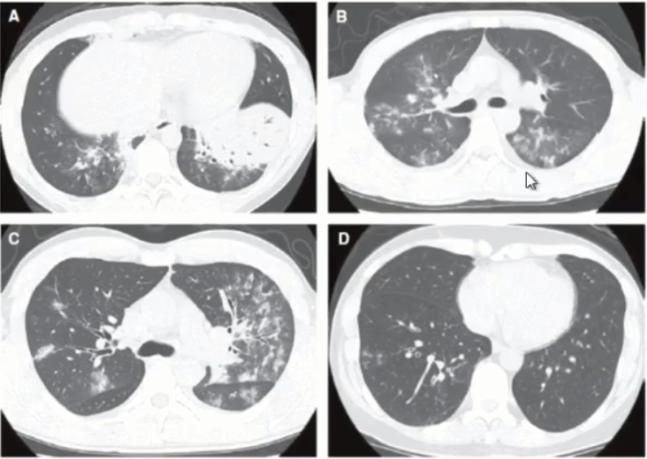

图11 有研究显示,肺炎支原体肺炎和肺炎链球菌肺炎实变发生率分别是61%和76%,两者之间的差异无显著统计学意义

图12 支原体肺炎影像学表现的多样性

图13 叶段实变往往是支原体肺炎进展期(重症)的表现